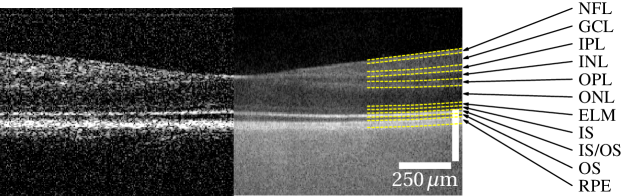

Using the high speed CMOS camera human retina was measured in vivo at million A-scans/s with off-axis reference (Fig. 5a, c, e). To enhance the imaging quality, which was compromised by the low signal level at the high imaging speed, volumetric data sets of OCT images were cross-correlated, shifted accordingly in all three dimensions, and averaged (Fig. 5b, d, f).

Given the acquisition speed, which was at significalty faster than that of commercially available OCT devices, image quality of the full-field system is remarkable. All retinal layers that are usually visible in OCT imaging can be clearly distinguished (see Fig. 5g). Intensities of the different layers above the RPE differ only slightly between FF-SS-OCT and scanned OCT. Below the RPE the choroid shows high signal intensities, but hardly any structures. Here mostly multiple scattered photons were detected due to the lack of a confocal gating. Photons from the strongly scattering RPE [23] or choroid are always assigned to depths higher than the depth of any of their scattering events and thus below the RPE. Therefore they disturb imaging of the choroid, but do not corrupt imaging of the neuronal layers.